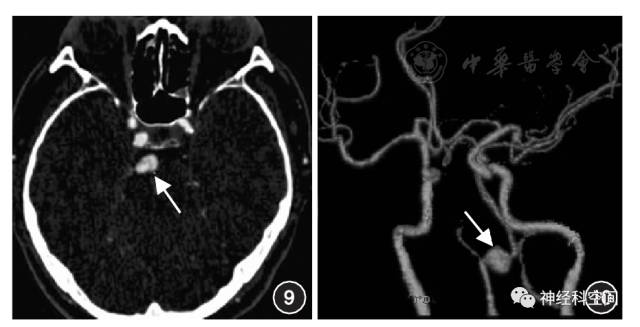

CT图像上观察到偏心性狭窄伴动脉外管径扩张,高度提示IAD病变。壁内血肿CT平扫呈新月形管壁病灶。CTA可显示由壁内血肿引起的管腔狭窄及血管外管径扩张,壁内血肿通常表现为等密度,注入对比剂后无强化。Lum等[39]在2009年对椎动脉夹层病变的研究显示,CTA图像上管壁增厚与管腔直径变化相比是一个更敏感的诊断征象。因此,对于部分管腔直径变化不明显的病例,尤其需要注意CTA薄层原始图像上的动脉管壁增厚表现。有研究显示,动脉外管径增宽与管壁增厚分别可见于93.3%和97.7%的椎动脉夹层患者,但这些征象也可见于非夹层病变[40]。在CTA图像上如果能观察到”双腔征”,对夹层病变可做出明确诊断。真腔一般较窄呈类圆形,为不完全闭塞的血管腔,有对比剂充盈,流速较高;假腔较宽,多呈新月形,为内膜夹层分离所致,由于腔内血流速度较慢,对比剂通过较慢而显示为稍低密度。内膜瓣或夹层动脉瘤的显示是IAD病变的可靠征象。内膜瓣的发现较壁内血肿少见,需要结合CTA薄层原始图像仔细观察(图9,图10)。

图9 基底动脉夹层动脉瘤CTA原始薄层图像,显示基底动脉管径不规则增粗,管腔内可见线状不规则等密度内膜瓣影,将管腔分割成2部分(箭头示)

图10 右侧椎动脉夹层动脉瘤(箭头示),CTA容积重建示右侧椎动脉局部管径增粗呈瘤样扩张